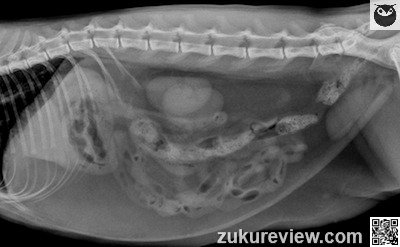

Physical exam reveals 5% dehydration and abdominal discomfort. Plain abdominal radiographs are shown below.

Which choice is the most appropriate step to take next?